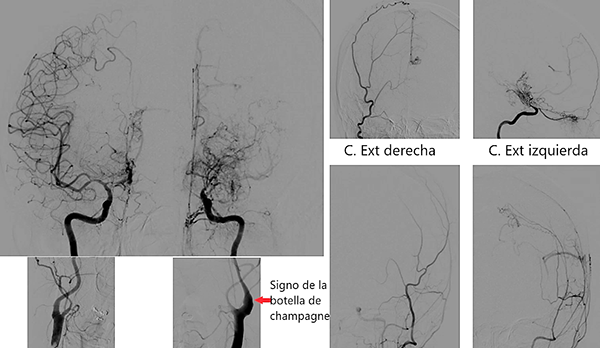

Caso clínico #3 (cirugía bilateral): GM femenino de 27 años, con antecedente de hipotiroidismo secundario a Enfermedad de Hashimoto; consultó por cuadro de parestesias y paresia leve braquial izquierda de más de 6 meses de evolución. La RMN evidencia pequeñas imágenes isquémicas en ambos centros semiovales a predominio derecho; la ARM y ADC muestran la estenosis severa de ambas arterias carótidas internas y ausencia del origen de ambas arterias silvianas con vasos de MM presentes; corresponde a un grado 3 de Suzuki (Fig. 6). Se realizó primero un bpTS derecho más EDMS y, a los 10 meses, otro bpTS más EDMS izquierdo con buena evolución en ambas revascularizaciones. La ADC alejada muestra franca mejoría de la perfusión cerebral bilateral más marcado a la izquierda (Fig. 7 y 8).

Fig. 6 Caso clínico #3. Preoperatorio. A la izquierda, la RMN evidencia pequeñas imágenes isquémicas en ambos centros semiovales mayor a derecha, la ADC muestran la estenosis severa de ambas arterias carótidas internas supraclinoidea y ausencia del origen de ambas arterias silvianas, vasos de MM presentes correspondiente a un grado 3 de Suzuki

Fig. 7 Caso clínico #3. Postoperatorio. ADC lado derecho que muestra buena perfusión cerebral del bpTS (las flechas rojas muestran el curso de la aTS) y la EMDS

Fig. 8 Caso clínico #3. Postoperatorio. ADC lado izquierdo con muy buena perfusión cerebral desde el bpTS (las flechas rojas muestran el curso de la aTS) y la EMDS